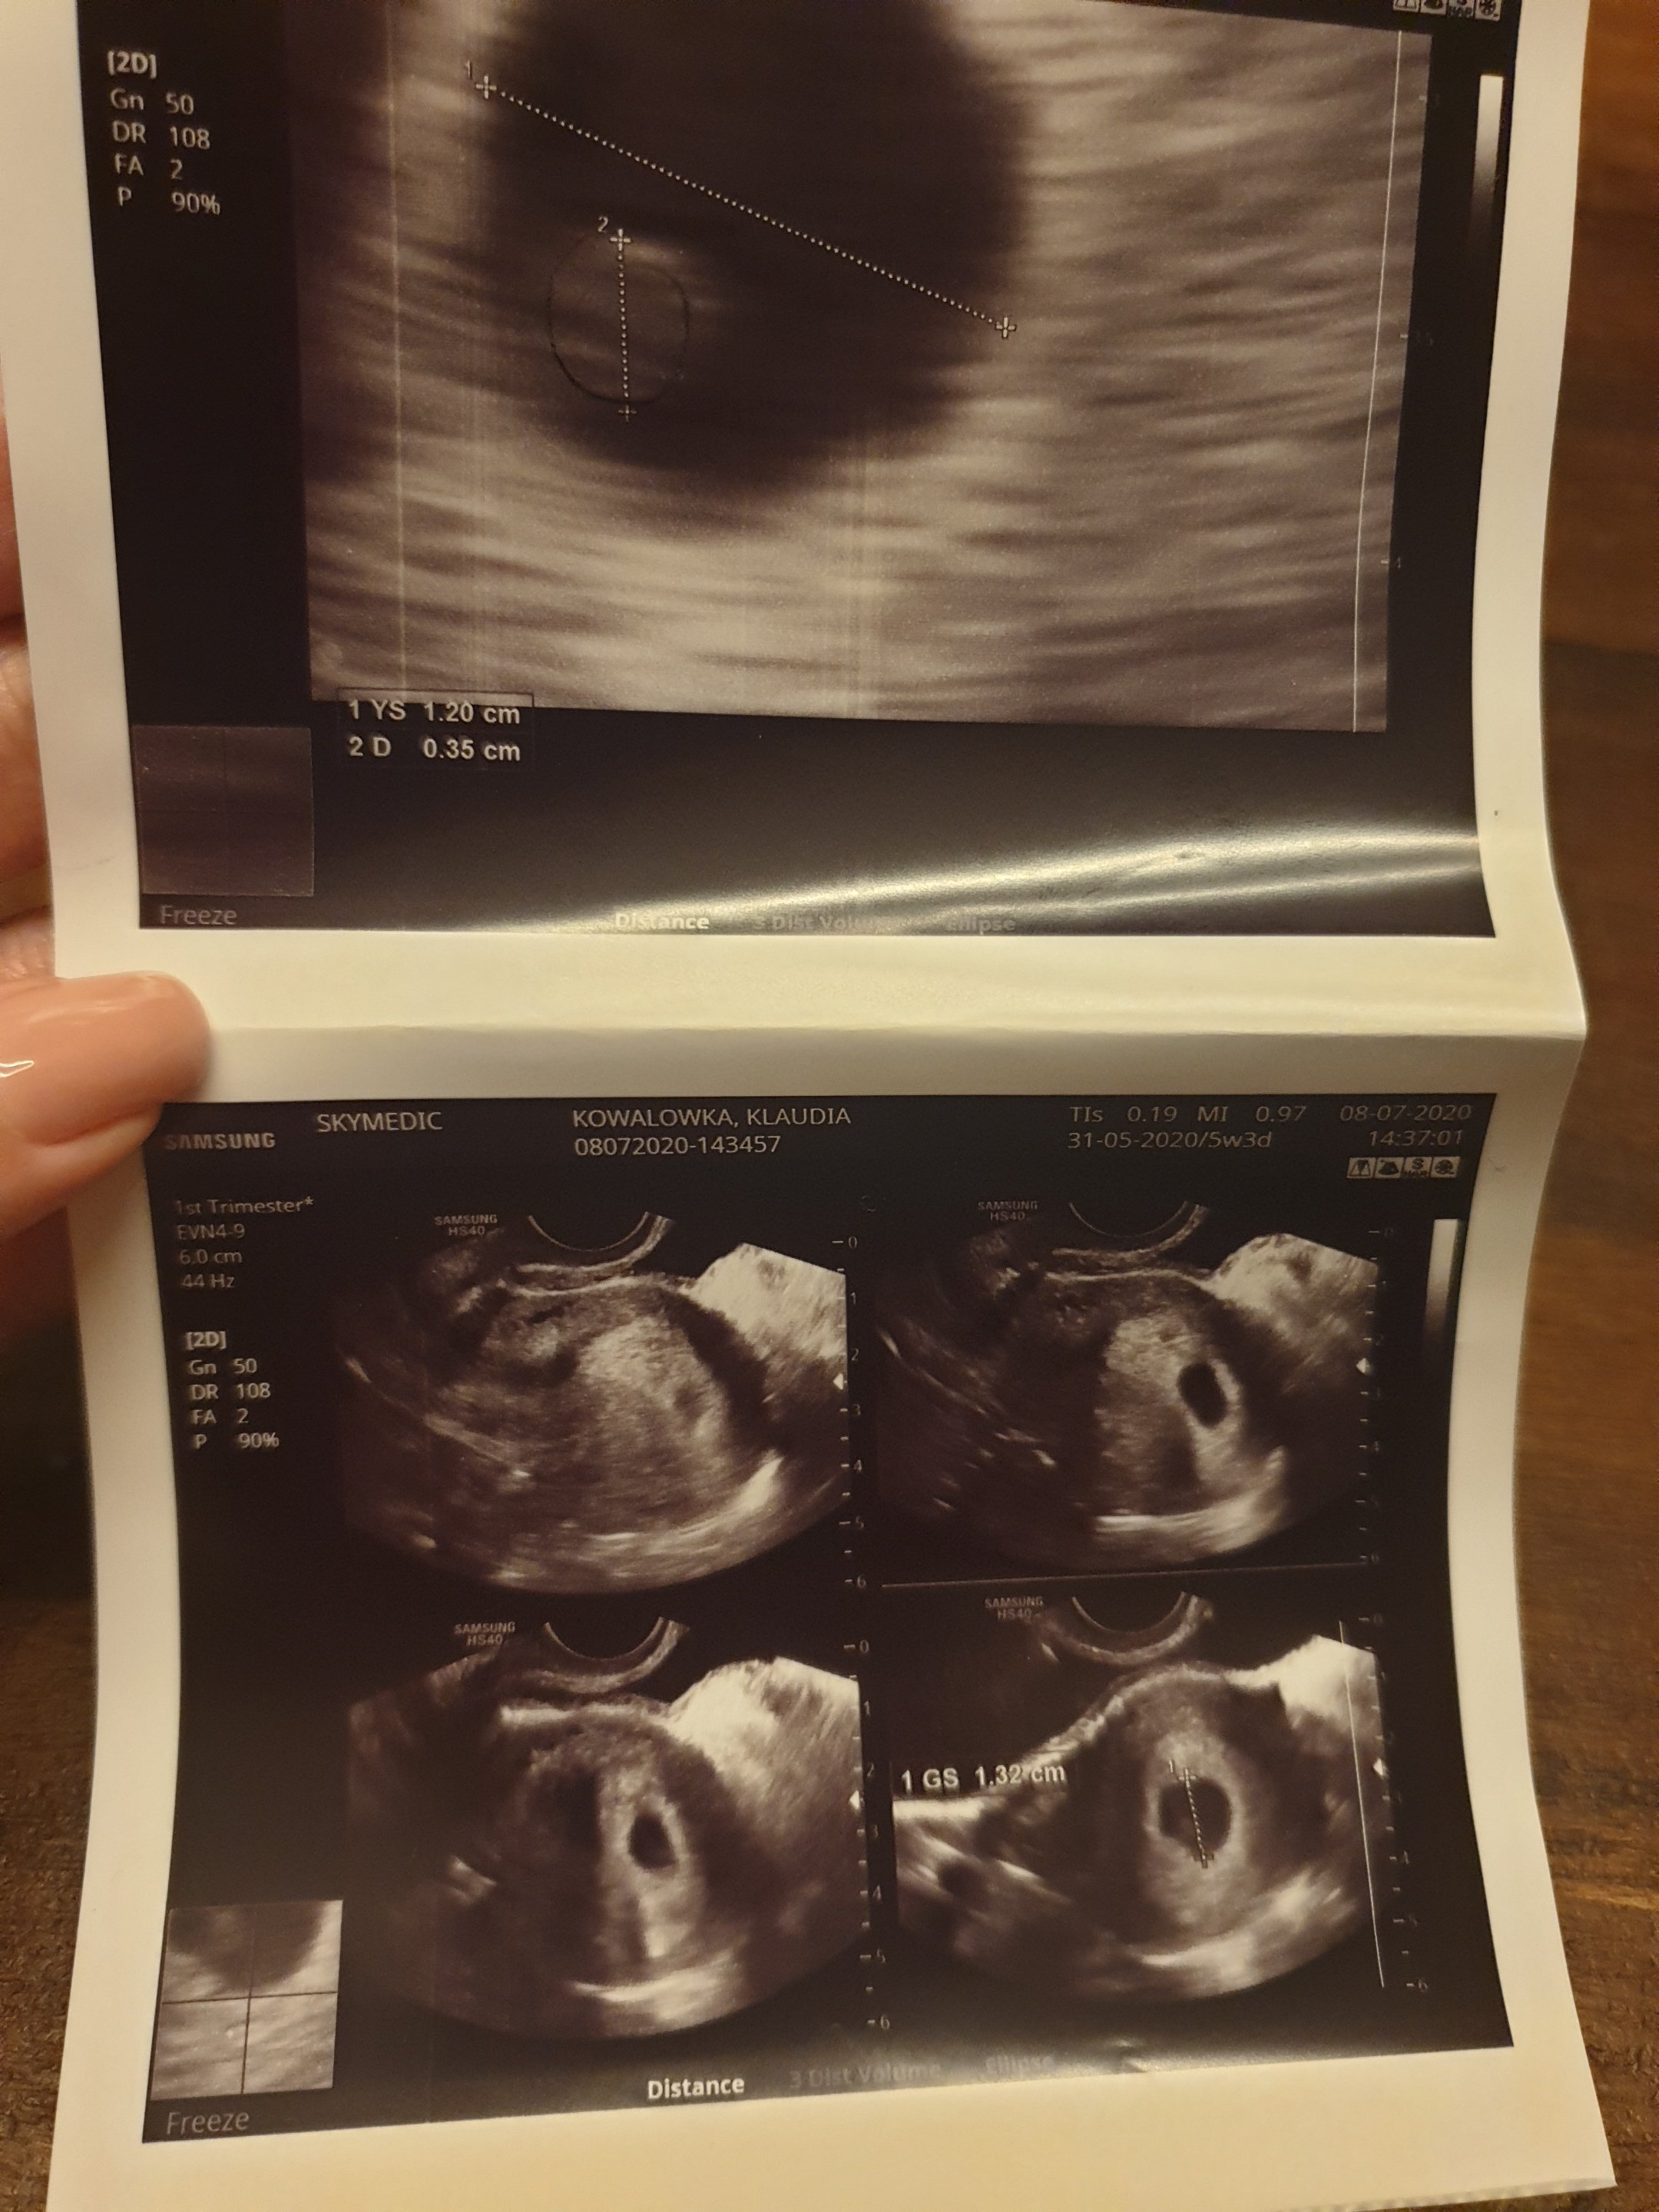

Witajcie dziewczyny. Błagam pomóżcie może któraś miała tak jak ja. 8 lipca (równe 3 tygodnie temu) byłam u ginekologa potwierdzić ciążę- 2 testy pozytywne, brak okresu (ostatnia miesiączka 31.05) z badań krwi wyszło, że jestem w 5 lub 6 tygodniu. Cykle mialam regularne co 22 dni (Tak wiem krótkie ale to norma tak naprawdę). Dzisiaj po 3 tyg udałam się znowu na wizytę kontrolną.. Pan doktor do mnie "To dzisiaj zobaczymy maluszka i posłucham serduszka" ... już po jego minie jak zaczął USG wiedziałam że coś jest nie tak. Brak echa serca, i wciąż tylko pęcherzyk CRL 0.66. Lekarz zaczął mnie uspokajać, że ciąża może być młodsza i mogę być w takim razie w 5 tygodniu a nie w 8-9 jak powinnam... Czy to możliwe? Cykle zawsze miałam regularne co do dnia. Kolejna wizyta za 2 tygodnie ale ja chyba oszaleje do tego czasu.. dodam że nie miałam żadnych objawów poza sennością